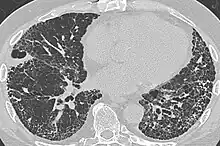

CT scan in a patient with usual interstitial pneumonia, showing interstitial thickening, architectural distortion, honeycombing and bronchiectasis.

Honeycombing or "honeycomb lung" is the radiological appearance seen with widespread fibrosis[1] and is defined by the presence of small cystic spaces with irregularly thickened walls composed of fibrous tissue. Dilated and thickened terminal and respiratory bronchioles produce cystic airspaces, giving honeycomb appearance on chest x-ray. Honeycomb cysts often predominate in the peripheral and pleural/subpleural lung regions regardless of their cause.

Subpleural honeycomb cysts typically occur in several contiguous layers. This finding can allow honeycombing to be distinguished from paraseptal emphysema in which subpleural cysts usually occur in a single layer.